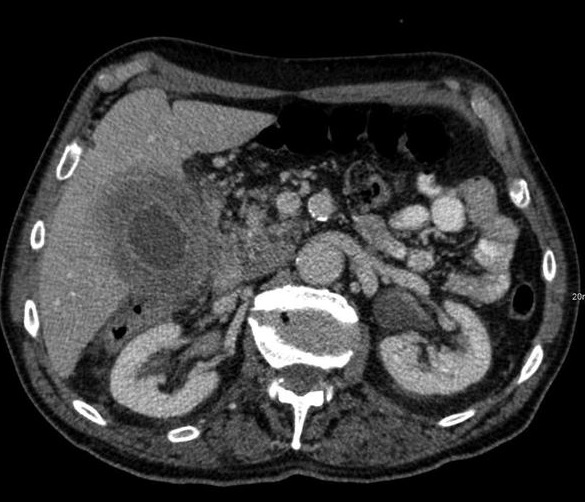

Vesicule biliaire distendue ,

Epaissisement irreguliairement de la paroi

vesiculaire et image hypodense de l'air intramural

et intra vesiculaire : Cholecystite emphysemateuse .

Image TDM en coupe axiale |

Image radiologique TDM

en coupe coronal a travers vesicule biliaire : La

vesicule est distendue , paroi epais et en presence

d'air intramural . Cholecystite emphysemateuse |